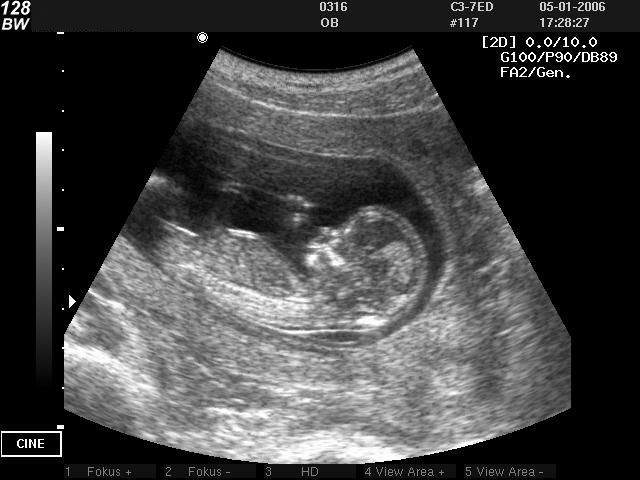

Но ведь это ужасно! — прервал я ученого. — Сейчас во всем мире очень модно ультразвуковое сканирование. Метод считается совершенно безвредным, поэтому его широко применяют для диагностики детей. «Просвечивают» ультразвуком даже беременных женщин, чтобы узнать пол будущего ребенка. Легкомыслие и самонадеянность «царей природы» просто поразительны. Они знают, что некоторые животные используют ультразвук как оружие: дельфины глушат им рыбу, кашалоты кальмаров и так далее. Но медики предложили больным подвергнуться подобному воздействию — и они охотно согласились, даже отдали своих детей на эксперименты с ультразвуком.